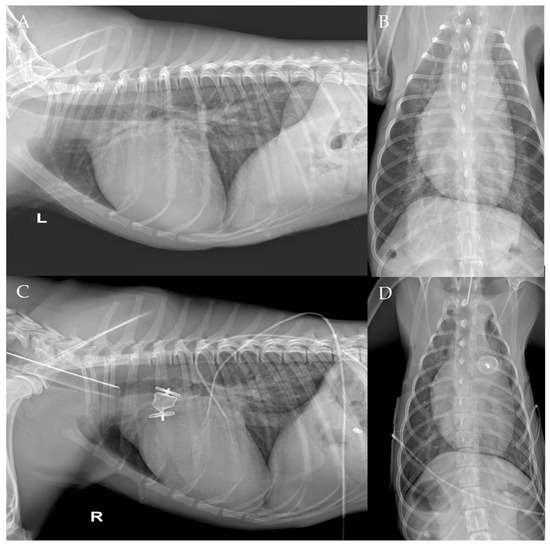

The thoracic radiographs performed before and just after the procedure showed a reduction in the cardiac silhouette as well as significant reduction of the over-circulation vascular pattern for all dogs (Figure 8, Figure 9, Figure 10, Figure 11 and Figure 12).

Figure 9. Pre-procedure (A,B) and post-procedure (C,D) left lateral and dorso-ventral thoracic radiographs of Case 2. L: left; R: right.